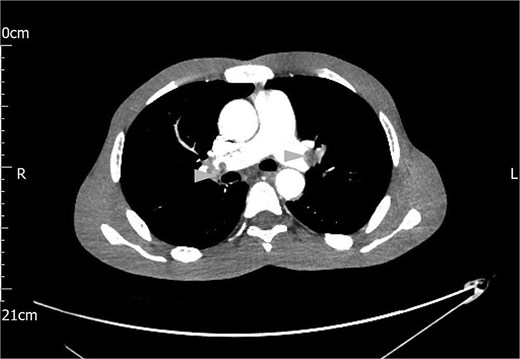

A computed tomography (CT) scan of the chest, abdomen and pelvis reported gross ascites, irregularity of the tail of pancreas not typical of pancreatitis, mesenteric soft tissue density, and bilateral thromboemboli in the main pulmonary arteries, as shown in Fig. 1.

Contrast CT scan of the chest showing bilateral pulmonary artery thromboemboli (arrow heads).